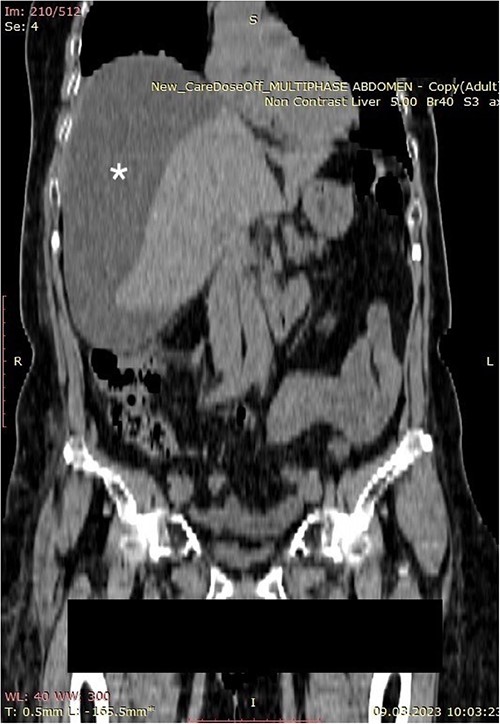

A 70-year-old female patient was transferred to our emergency department from another hospital with abdominal pain and vomiting in the past 2 weeks. The patient presented with clinical signs of acute abdomen. Physical examination showed diffuse abdominal tenderness. Abnormal laboratory findings comprehended Leucocyte count of 12.01 (3.5–10.0 × 109 g/L), Thrombocyte count of 456 (150.0–300.0 × 109 g/L), Neutrophil count of 9.7 (1.2–8.0 × 109 g/L), serum direct bilirubin value of 11.10 (0.0–8.6 mmol/L), and C-reactive protein value of 258 (0.0–5.0 mg/L). An abdominal computerized tomography (CT) scan revealed a large collection of fluid in the right hemiabdomen (Figs 1 and 2) and free gallstones in the abdominal cavity (Fig. 3).

Computerized abdominal tomography (coronal scan) showing a large biloma (asterisk).